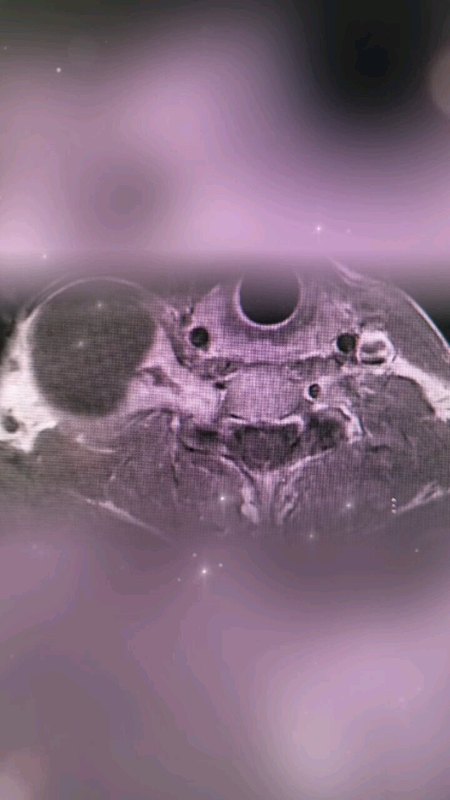

脊柱也長腫瘤嗎?